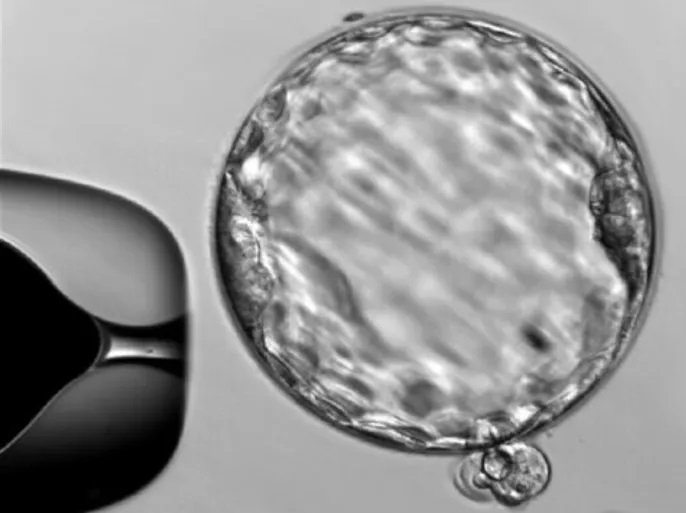

العلماء: أجنة البشر قادرة "السبات الجنيني".. "أمخسور"

الخلايا البشرية لديها هذه القدرة الكامنة، التي يمكن استغلالها في المستقبل لتعديل الجداول الزمنية لنمو الأجنة في مراحلها المبكرة (أسوشيتد برس)

عبد الله طه